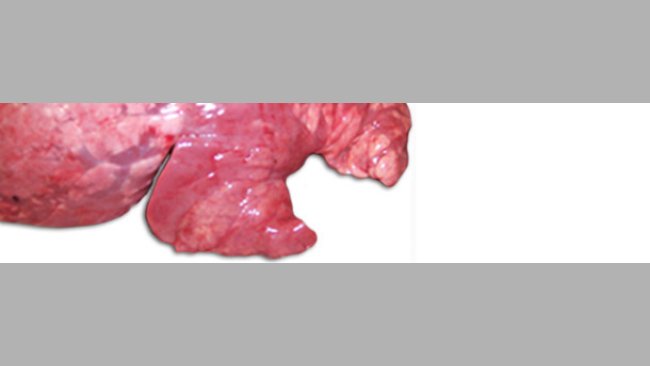

Una de las coinfecciones más frecuentes en las granjas porcinas en casos de CRP es la producida por M. hyopneumoniae y PRRSV (figura 2). En aquellos casos en los que se ha diagnosticado esta coinfección se ha observado una correlación positiva entre los animales seropositivos a cada uno de los dos agentes, es decir, la mayoría de los animales positivos a PRRSV lo son también a M. hyopneumoniae. Además, se ha podido comprobar que M. hyopneumoniae prolonga e incrementa la neumonía producida por el PRRSV, lo que podría ser debido a que en los animales coinfectados con ambos patógenos se produce un aumento de citoquinas proinflamatorias, como IL1-β, IL-8 y TNF-α, que incrementan la reacción inflamatoria a nivel pulmonar, pero también un aumento en la síntesis de la IL-10, que es una citoquina antiinflamatoria que inhibe y modula la producción de otras citoquinas y que permitiría perpetuar el daño a nivel pulmonar al impedir que se desencadenara una reacción inflamatoria descontrolada. La IL-10 a su vez también es capaz de modular la respuesta inmune del animal, lo que junto con la activación de otros mecanismos, altera la respuesta inmune adaptativa, favoreciendo que el patógeno pueda seguir ejerciendo su acción en el pulmón durante más tiempo.